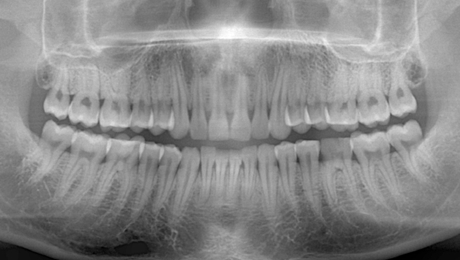

最先端のデジタルテクノロジーを駆使し、より少ないX線で高解像度な画像が得られる、CT撮影、パノラマ撮影が可能なレントゲン装置です。

さらに洗練された多彩な画像処理により、多角的な診査を行うことが出来ますので、的確な診断を行う上で重要な役割を担っています。

φ40×H40mmの局所領域から、全歯列対応のφ100×H80mmまで鮮鋭なCT画像が撮影可能です。

根管治療、歯周病、親知らず、インプラント、上顎洞、顎関節などの治療においてより正確な診査、診断が行えます。

パノラマ画像